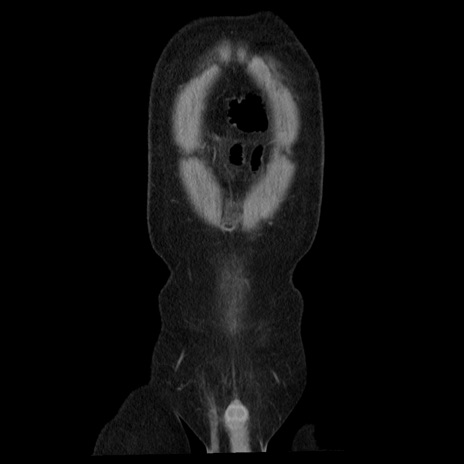

横断像

【症例】40歳代男性

【現病歴】2日前から胃痛あり。徐々に周期的な激痛に変化した。本日になっても激痛があるため受診。

【身体所見】意識清明、BT 38-39℃台あり、腹部:膨満、やや硬、右下腹部に圧痛あり。

【データ】WBC 8500、CRP 23.26